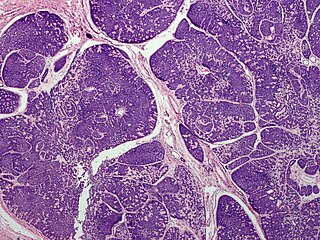

| Micrograph of a dermal cylindroma. H&E stain. | |

In dermatologic pathology, a dermal cylindroma, also dermal eccrine cylindroma or cutaneous cylindroma[1]: 666 ) and (less specifically) cylindroma, is a benign adnexal tumor[2] that occurs on the scalp and forehead.

Multiple cylindromas may grow together in a "hat-like" configuration, sometimes referred to as a turban tumor.[3] Cylindromas are uncommon dysplasias of skin appendages.[4]

They lack of a significant number of lymphocytes; this differentiates them from spiradenomas.

Dermal cylindroma. Puzzle-like distribution of tumour foci.

Dermal cylindroma. Hyaline droplets visible in lobules.

Dermal cylindroma, micronodular type.